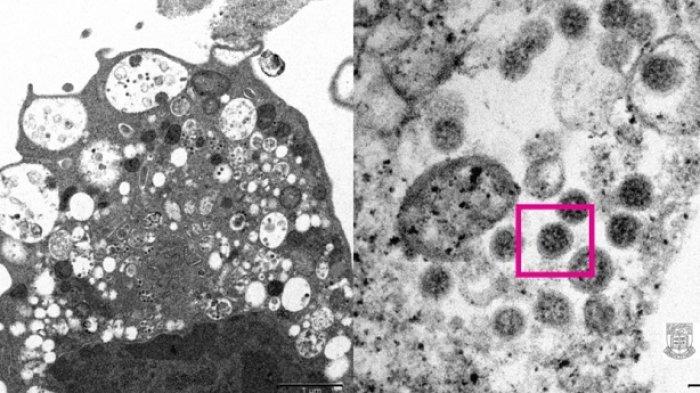

Virus Corona

:quality(30):format(webp):focal(0.5x0.5:0.5x0.5)/wartakota/foto/bank/originals/penampakan-omicron.jpg)